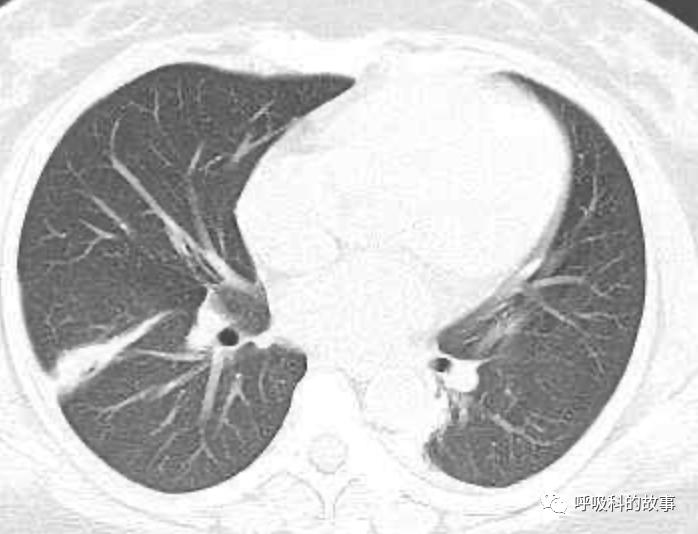

患者发热后行胸部CT检查(6月21日,住院第13天),可见两下肺有条片影,当时考虑是肺炎引起的发热。

可是在6月26日(往院第18天)仍持续发热的情况下复查肺部CT,肺部病灶已明显吸收了。那么患者发热的原因到底是什么呢?为什么患者高热的情况下血白细胞不升反降,C反应蛋白也没有明显增高?这个时候消化科医生也迷茫了,这可怎么办?于是请感染科和呼吸科医生一起会诊,共商计策。